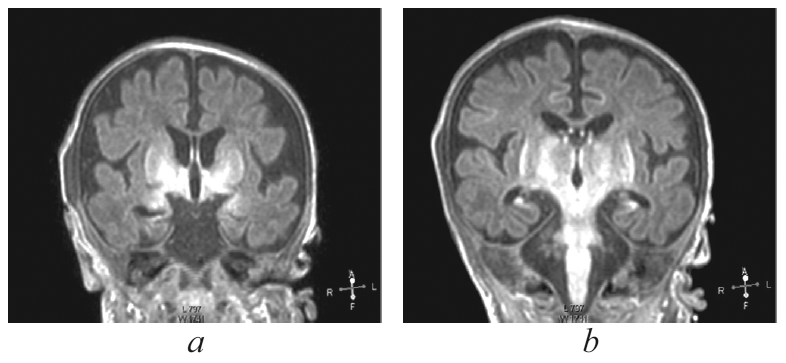

В статье кратко приведены литературные данные и описание клинического динамического наблюдения пациента с тяжелым гипоксическим повреждением головного мозга (от неонатального периода до 4-го месяца жизни) в условиях отделения реанимации и интенсивной терапии новорожденных. Представлены описание клинической картины, особенности пароксизмальных состояний и антиэпилептической терапии, динамика данных нейровизуализации, электроэнцефалографических феноменов, регистрируемых у пациента с церебральной депрессией и структурными церебральными повреждениями. Показана значимость электроэнцефалографического исследования в условиях отделения реанимации как информативного метода оценки церебральной активности у детей раннего возраста с синдромом угнетения центральной нервной системы. Дезорганизация фоновой активности, свидетельствующая о структурных церебральных повреждениях, длительное персистирование медленноволновой активности, выявление эпилептических изменений в виде генерализованных вспышек заостренных волн в диапазоне тета, паттерн альфа-комы, впоследствии сменившийся супрессией фонового паттерна у пациента, являются типичными электрофизиологическими нарушениями, регистрирующимися при тяжелой гипоксической энцефалопатии. В условиях ограничения возможностей визуальной диагностики пациента с нарушением сознания электроэнцефалография остается единственным методом получения информации о функциональном состоянии головного мозга, а данные, полученные при исследовании, — важным прогностическим критерием.